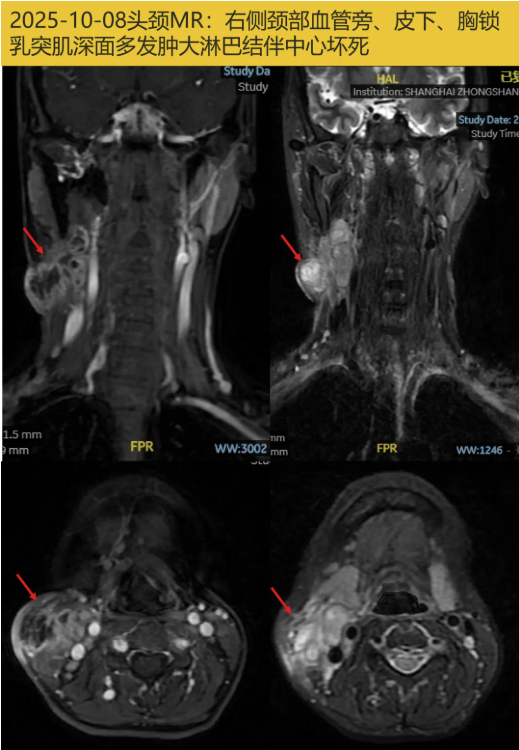

头颈部软组织MRI(2025-10-08): 右侧颈部血管旁、皮下、胸锁乳突肌深面多发肿大淋巴结伴中心坏死,感染可能,MT待排;右侧颈根部稍大淋巴结。